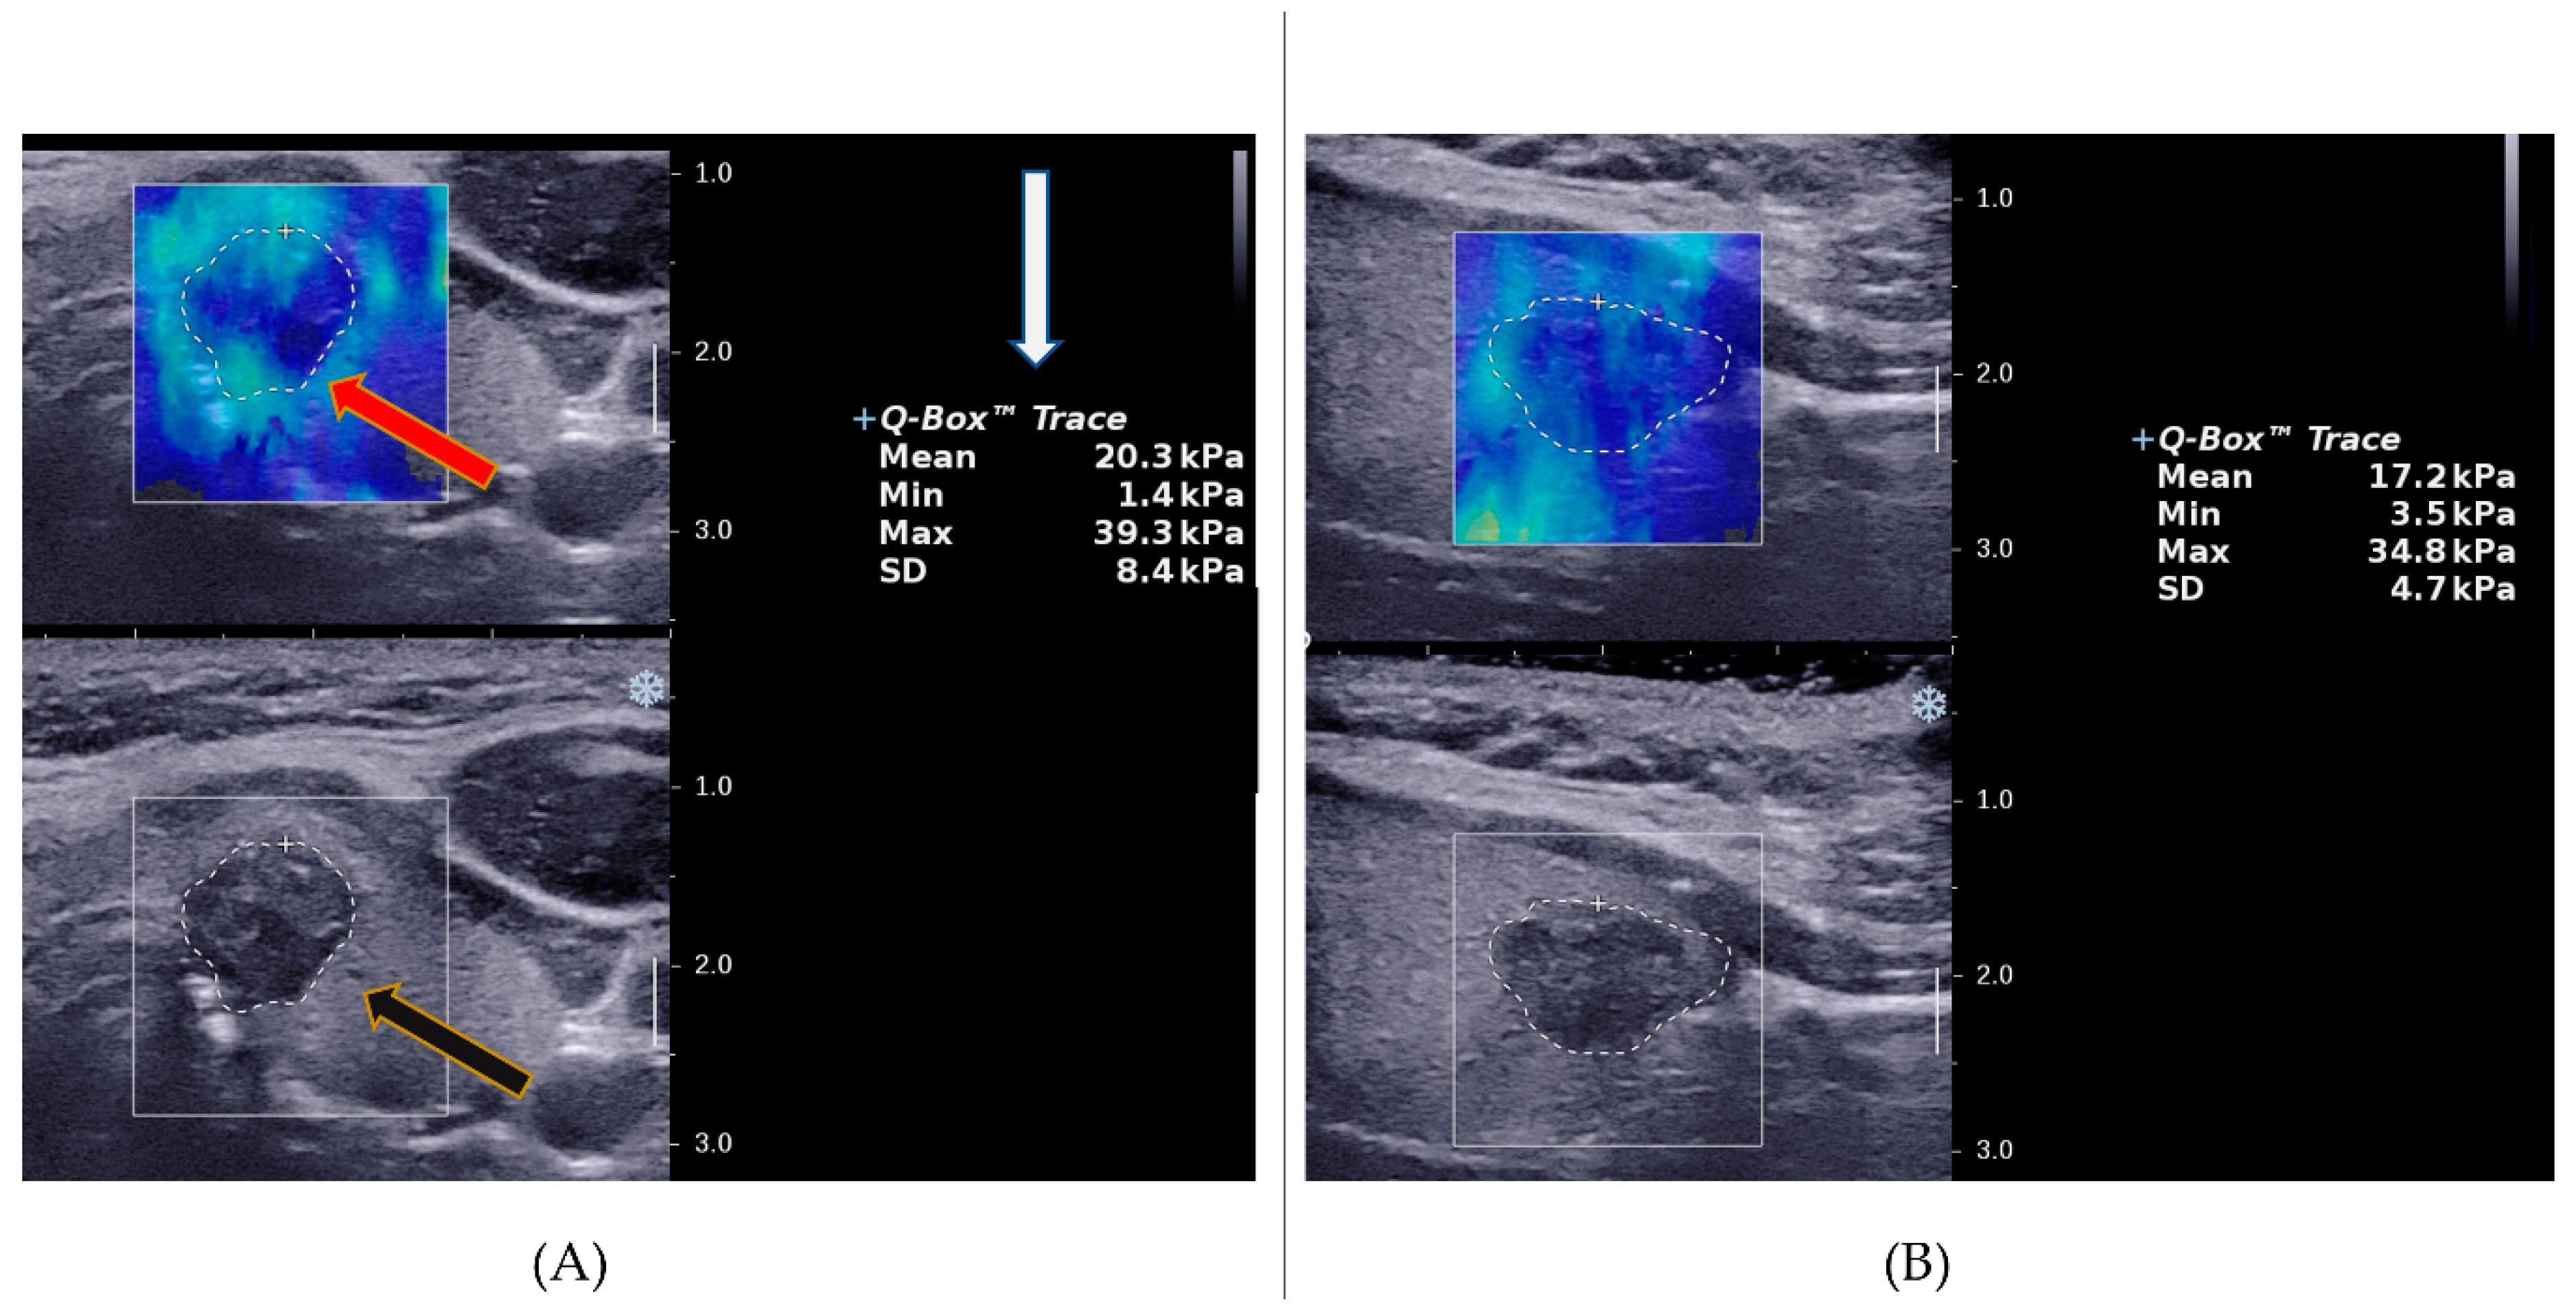

2.2. Ultrasound Imaging Procedures

2.3. Image Analysis Procedures